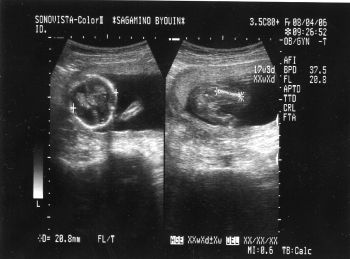

| 2006-06-07 初エコー | 2006-08-04 日本で | |